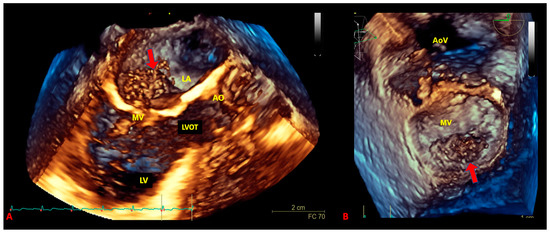

- Guta, A.C.; Badano, L.P.; Ochoa-Jimenez, R.C.; Genovese, D.; Previtero, M.; Civera, S.; Ruocco, A.; Bettella, N.; Parati, G.; Muraru, D. Three-dimensional echocardiography to assess left ventricular geometry and function. Expert Rev. Cardiovasc. Ther. 2019, 17, 801–815. [Google Scholar] [CrossRef] [PubMed]

- Asch, F.M.; Bieganski, S.P.; Panza, J.A.; Weissman, N.J. Real-Time 3-Dimensional Echocardiography Evaluation of Intracardiac Masses. Echocardiography 2006, 23, 218–224. [Google Scholar] [CrossRef]

- Gok, G.; Elsayed, M.; Thind, M.; Uygur, B.; Abtahi, F.; Chahwala, J.R.; Yıldırımtürk, Ö.; Kayacıoğlu, İ.; Pehlivanoğlu, S.; Nanda, N.C. Incremental value of live/real time three-dimensional transesophageal echocardiography over the two-dimensional technique in the assessment of primary cardiac malignant fibrous histiocytoma. Echocardiography 2015, 32, 1164–1170. [Google Scholar] [CrossRef]

- Reddy, V.K.; Faulkner, M.; Bandarupalli, N.; Nanda, N.C.; Singh, P.; Dutta, R.; Singh, A.; Pothineni, K.R.; Dod, H.S.; Bhardwaj, R.; et al. Incremental Value of Live/Real Time Three-Dimensional Transthoracic Echocardiography in the Assessment of Right Ventricular Masses. Echocardiography 2009, 26, 598–609. [Google Scholar] [CrossRef]